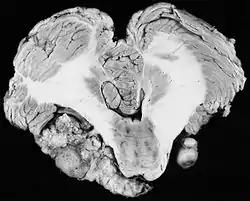

![]() ورم العصب السمعي ثنائي الجانب في مريض يعاني من النوع الثاني من الورم العصبي الليفي ورم العصب السمعي ثنائي الجانب في مريض يعاني من النوع الثاني من الورم العصبي الليفي | |